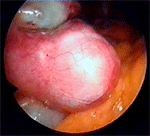

По време на хирургическа интервенция се откриват два вида хидросалпинкс – тънкостенен и дебелостенен.

При тънкостенния тръбата е силно дилатирана и изпълнена с бистра течност, което и дава прозрачен вид.

При дебелостенния тръбата изглежда зачервена, непрозрачна, луменът е тесен и съдържа малко количество течност. Този вид на маточните тръби е свързан с хроничен възпалителен процес. Хирургическото лечение на дебелостенен хидросалпинкс чрез неосалпингостомия е абсолютно безплодно (6.).

Дебелостенен хидросалпинкс